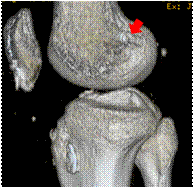

腱を移植するために長方形に作成した骨孔